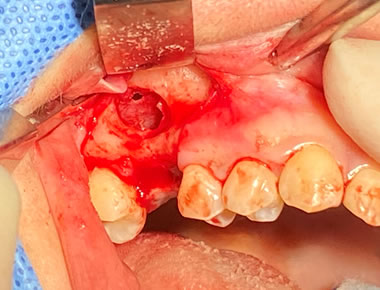

上顎外側骨隆起 症例1

咬合の応力は上顎の場合、必ずしも口蓋正中に集中するわけではありません。

歯列や歯牙の傾斜の角度により外側に分散することがあります。

その場合、上下とも外側に大きな骨隆起を生じます。

これが大きくなりすぎると食物残渣の停滞を引き起こし口腔内の不快感、口腔衛生状態の悪化につながります。

治療は外科的に除去することが第一選択肢となります。

料金

静脈内鎮静法による麻酔代込:約17万円(保険適用外)